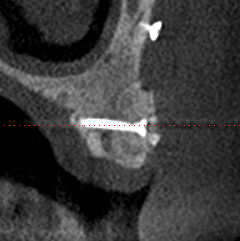

26/04/2010 à 14h00

la suite radiologique du cas, implantation prévu le 6 mai

Biobank   6 mois dbkbbo - Eugenol

Biobank 6 mois  2 cj54ky - Eugenol

Biobank 6mois 3 ck56hx - Eugenol

Biobank 6 mois 4 giwlus - Eugenol

Post1 y45ukn - Eugenol

Post2 caxl5b - Eugenol

Post3 ovhzhy - Eugenol